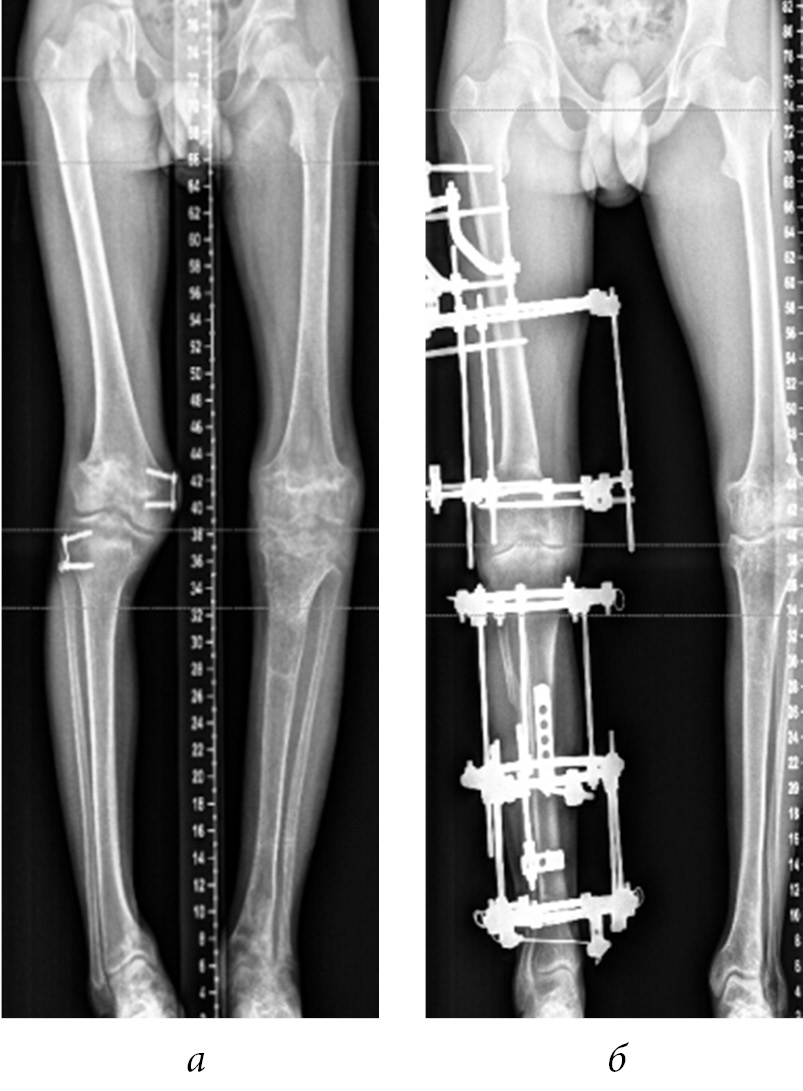

In four cases among those presented, the controlled growth technique was used to prevent the recurrence of deformity and correct the length of the fibula in dysfunction of the tibial growth zones (Fig. 6). After analyzing the literature data and own cases (recurrence of valgus deformity of the knee joint 2 and 4 years after corrective osteotomy of the femur and tibia), we concluded that temporary epiphysiodesis of the remaining functioning sections of growth zones is advisable. However, given the small number of cases, it is premature to evaluate the long-term results of temporary epiphysiodesis.

Fig. 6. Consistent application of controlled growth techniques (a) and compression-distraction osteosynthesis (b) to correct deformities of segments of the right lower limb